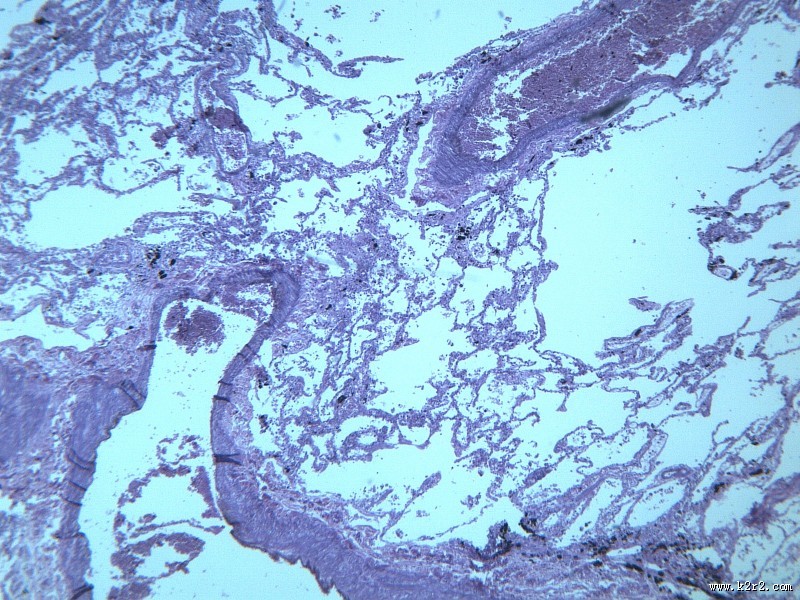

慢性支气管炎 - 第5张

慢性支气管炎

图集中 / 共有 12 张图片

显微切片

chronic bronchitis

支气管炎